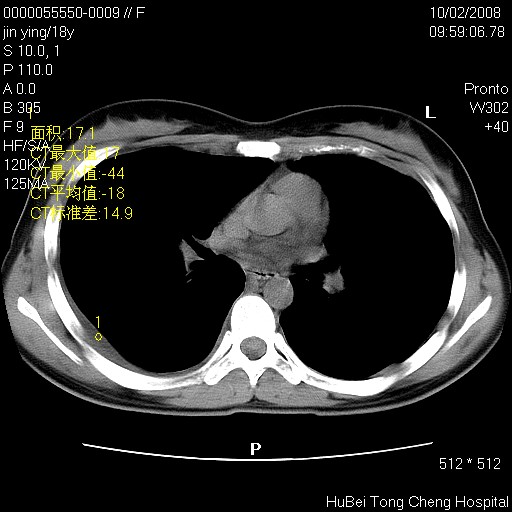

患者 女,18y。发热十余天,伴咳嗽。pe:t39⒈℃,bp 110/80mmhg,p 86次/min。神清,精神欠佳。双肺可闻及少许湿罗音。既往史不详。

临床诊断:肺部感染?

胸部ct轴位平扫(层厚10mm,螺距1.5,重建间隔10mm),图像如下: